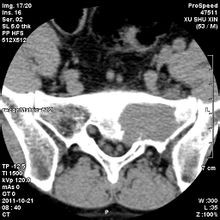

骶骨常見的良性腫瘤有骨母細胞瘤(成骨細胞瘤)、骨巨細胞瘤和動脈瘤樣骨囊腫等,常見的骶骨惡性腫瘤有脊索瘤、軟骨肉瘤等。手術(shù)治療是多數(shù)骶骨腫瘤的首選方案,該區(qū)域手術(shù)時出血多且不易止血,曾被視為手術(shù)禁區(qū)。